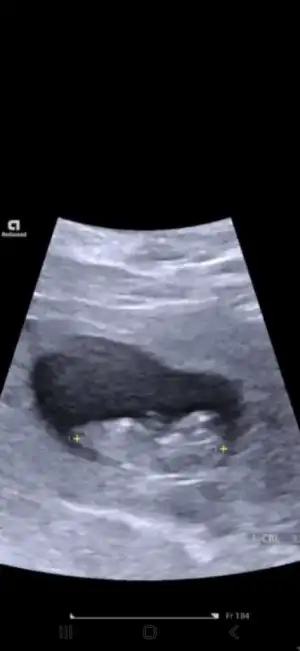

Benimde 13+1 de karından ultrason ile bakıldı tahmin de bulunabilir misiniz 🙏